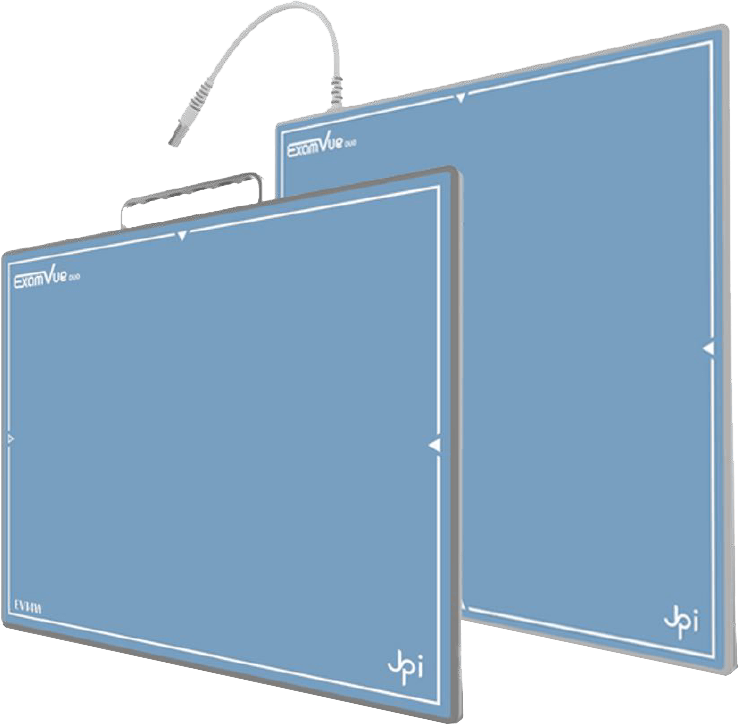

Incorpore la última tecnología en Radiología Digital con nuestra gama de Detectores Flat Panels.

Disponibles para Radiología General, Móvil, Mamografía, Neonatología y Fluoroscopía.

Explore nuestra gama de detectores innovadores y mejore la eficiencia y precisión en sus procedimientos radiológicos.

- Amplia variedad, para todas las prácticas.

- Repertorio completo de herramientas.

- La mejor calidad de imagen.